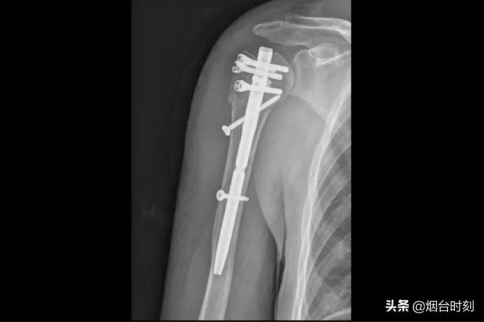

术前,将患者骨折部位的薄层CT扫描影像学信息进行三维重建,据此打印出骨折模型。手术时,医师根据术前设计,有条不紊地展开手术,将肱骨髓内针植入。术后,患者的肩关节性能常态,修复优良,到达了之前预料的创伤小、修复快并且减小围术期并发症等目标。

患者的术后影像。